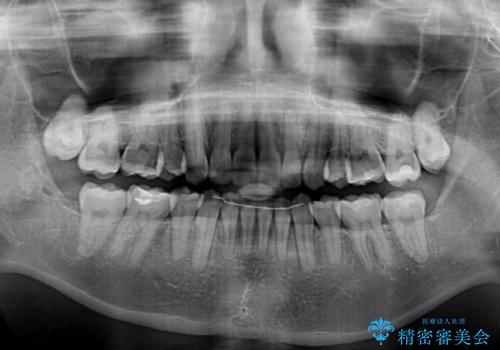

2年ほどインビザラインを使用しましたが、どうしても歯の移動がマウスピースに追随せず、全顎ワイヤー矯正へ切り替えました。

ワイヤー装着後は2年弱で、しっかりと仕上げることができました。